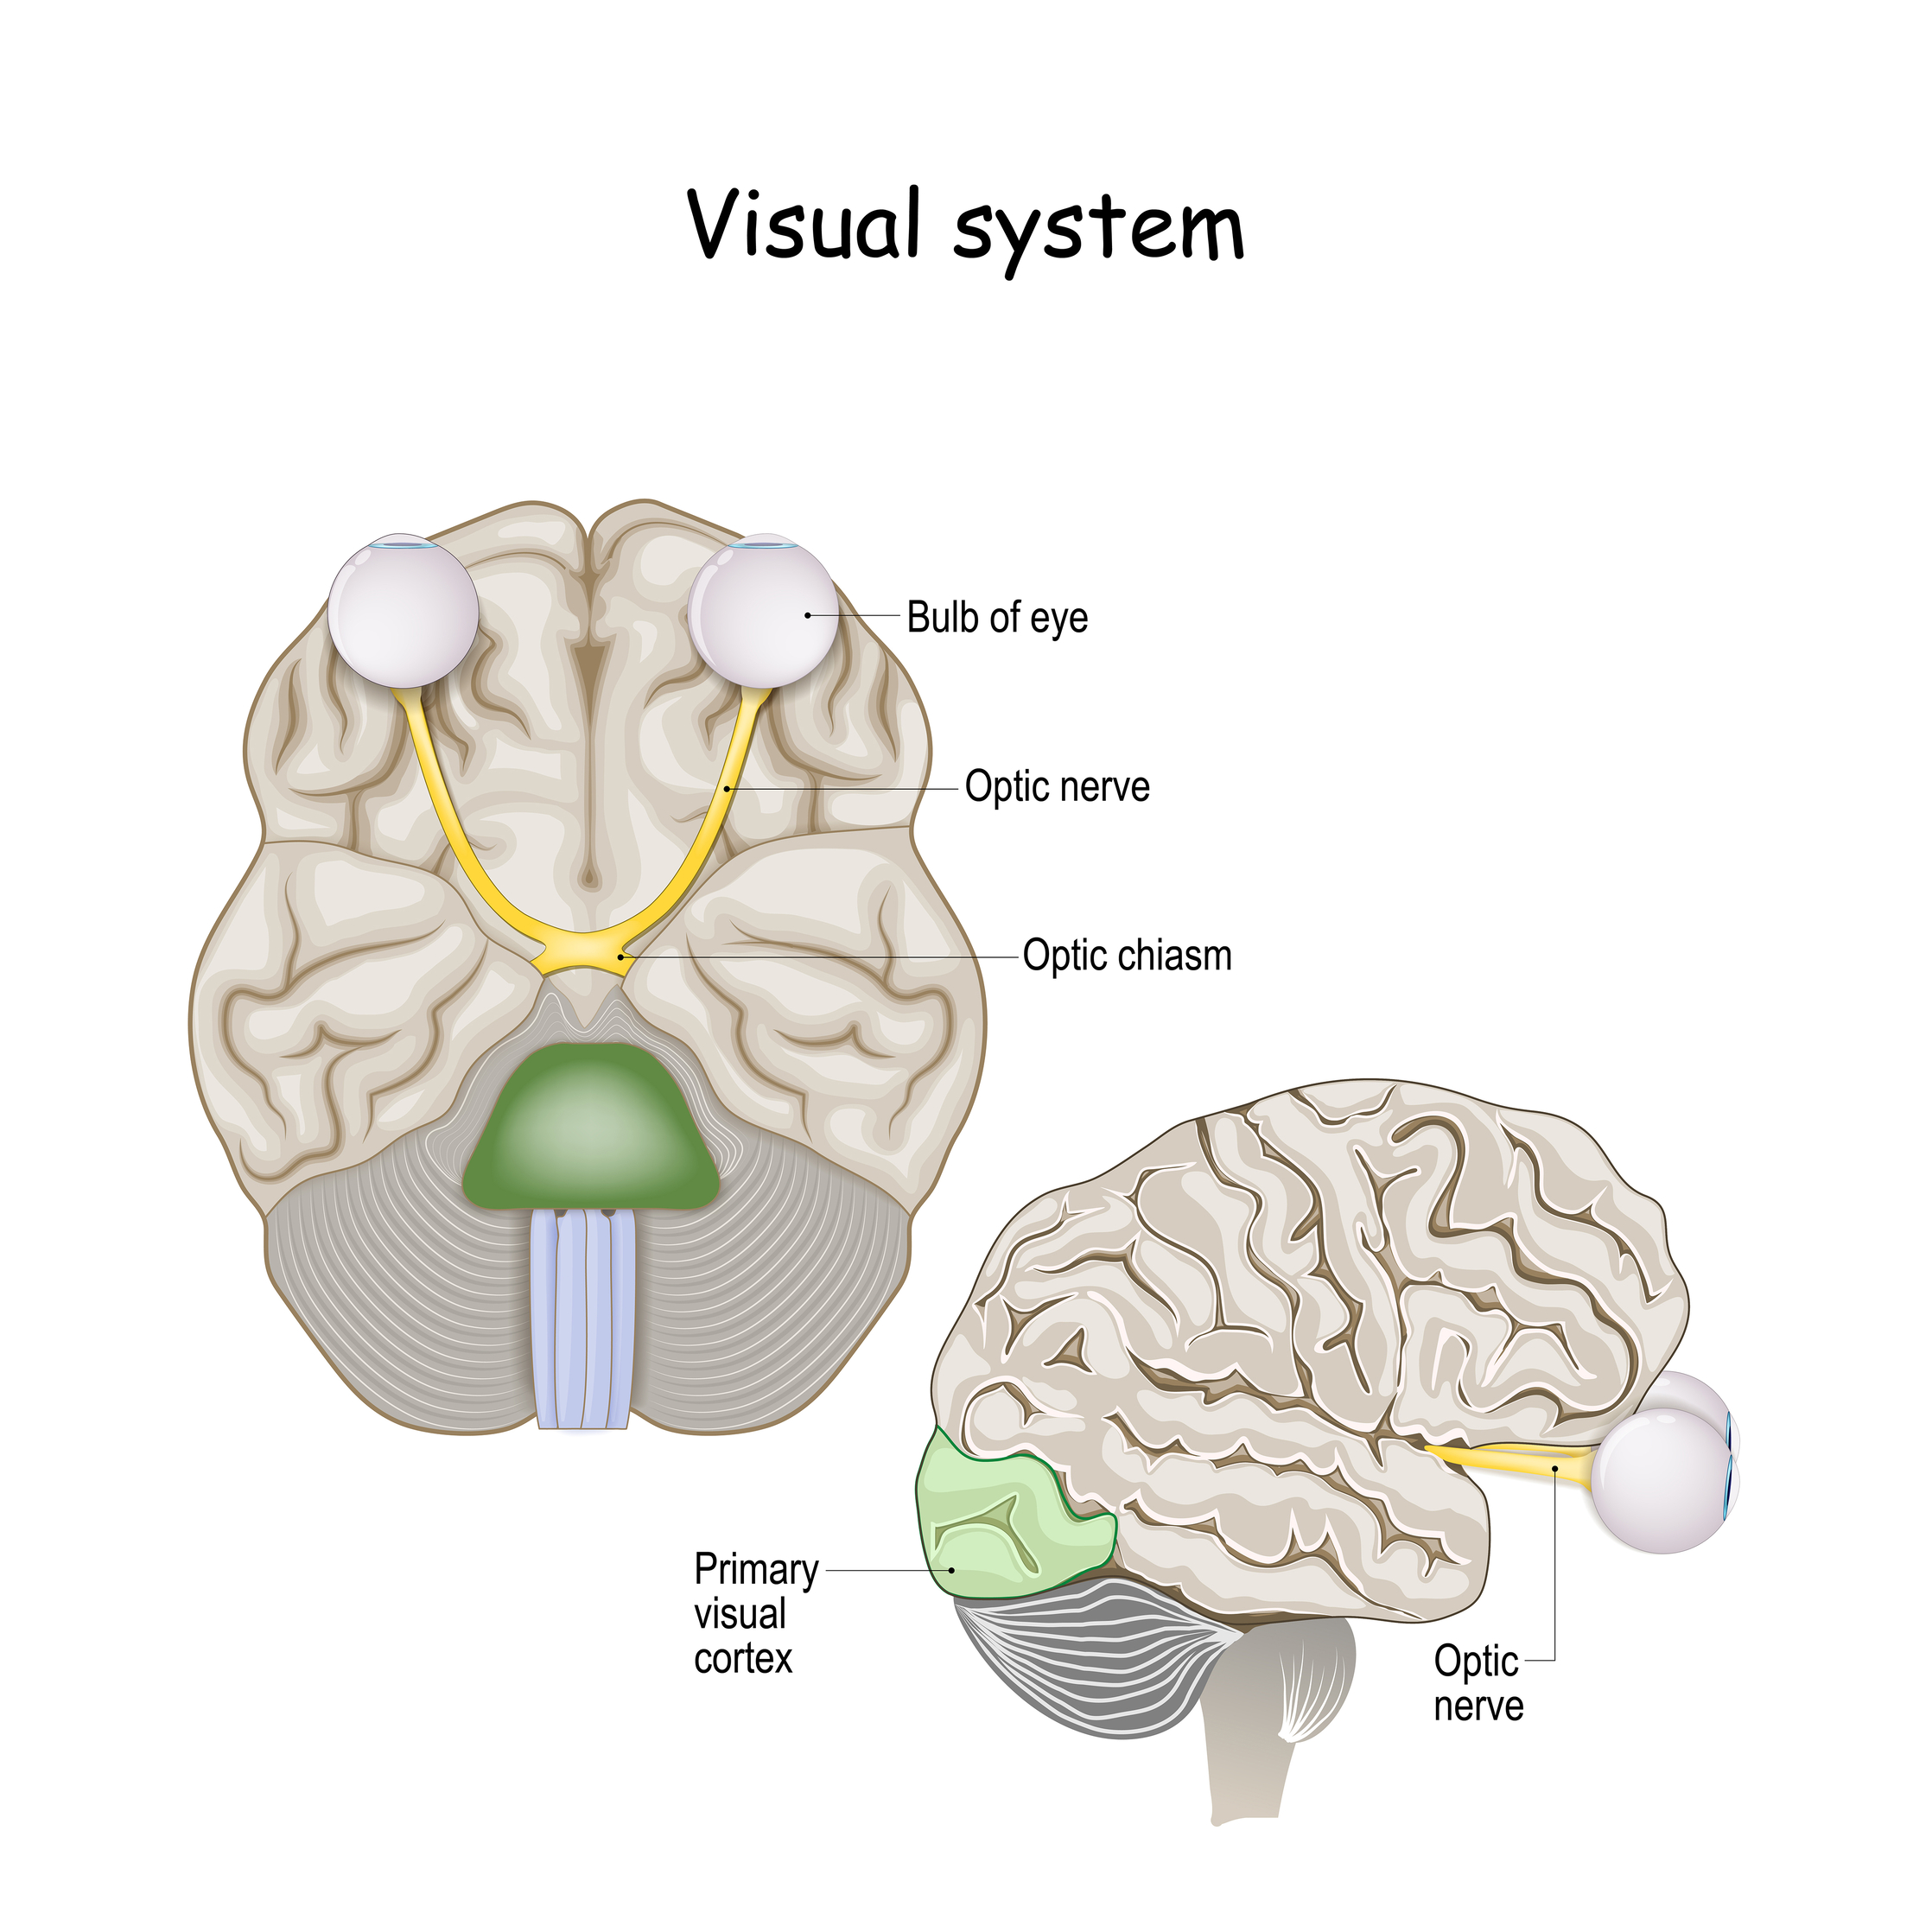

- Eyes (Visual System): Our eyes are super important for balance. They look around and help us figure out where we are and how we're moving.

Our brain uses the information from our inner ear to help control our muscles and even our eyes…

So we can stay balanced and see clearly even when we're moving.

All these parts – our eyes, inner ear, and body nerves – work together to help us stand up straight and not fall over.